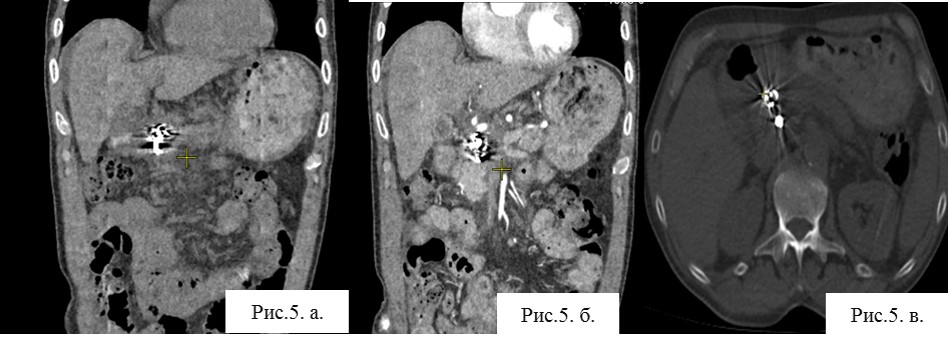

Результаты КТА: состояние после РЭО желудочно двенадцатиперстной артерии. Артефакты от спиралей, имплантированных в полость ложной аневризмы. Признаки тромбоза верхней брыжеечной вены (ВБВ). Псевдокиста перешейка поджелудочной железы. Портальная гипертензия. Билиарная гипертензия. Асцит.

Рис. 5. а, б. КТ с болюсным контрастированием. Артериальная фаза. Визуализация области окклюзии. Артефакты от имплантированных в полость образования спиралей. Визуализация спирали, находящейся в области окклюзии.

Рис. 5 в. КТ без режима контрастирования. Визуализация спирали, находящейся в области окклюзии.